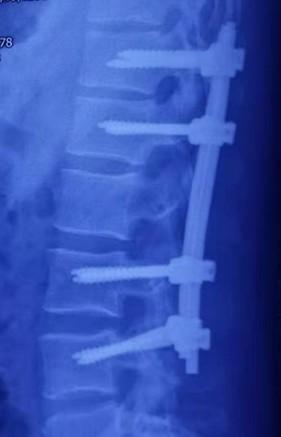

手术全程应用进口手术显微镜,使用微创器械小心打开硬膜、脊髓后正中切开并仔细暴露肿瘤,大小约2.2cm×2.7cm×6.5cm,双极电凝保证止血和手术视野清晰,小心保护神经脊髓组织,打开肿瘤外壁,小心清理其内容物,包括钙化组织、羊脂样瘤组织、毛发、脂肪瘤等。根据病变以上表现,术中即明确病变性质,确诊为成熟性畸胎瘤,仔细修复硬膜及棘突组织,安置钉棒固定系统(图片2)。

术后X线显示钉棒固定系统位置良好